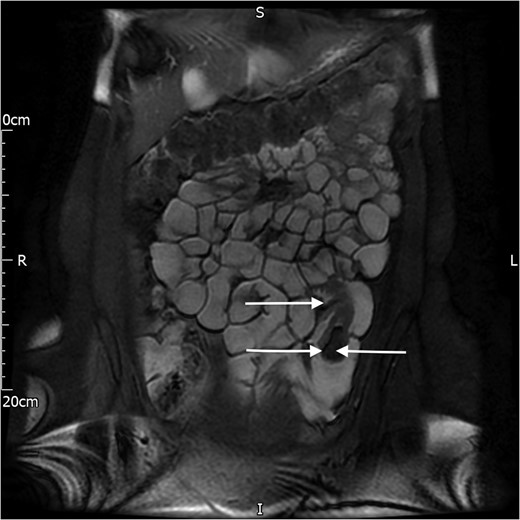

A 21-year-old lady with past medical history of psoriasis, urolithiasis and allergic rhinitis presented with 4-week history of colicky and intermittent epigastric pain associated with single and isloated episode of vomiting and diarrhoea. On presentation, she was found to be afebrile with normal observations. Clinical examination revealed, soft, non-tender abdomen with normal haematological markers. Ultrasonography of the abdomen demonstrated a hyperechoic lesion within the lumen of jejunum measuring ~1.6 cm (transverse) × 3.6 cm (longitudinal) in size, raising the suspicion of polypoid tumour and intussusception. Magnetic resonance (MR) enterography exhibited 2 cm circumferential lipoma, with 7 cm intussusception of the small bowel in the left upper quadrant (Fig. 1).

MR image of the lipoma (single arrow, left side) and the intussusception (double arrow, right side).